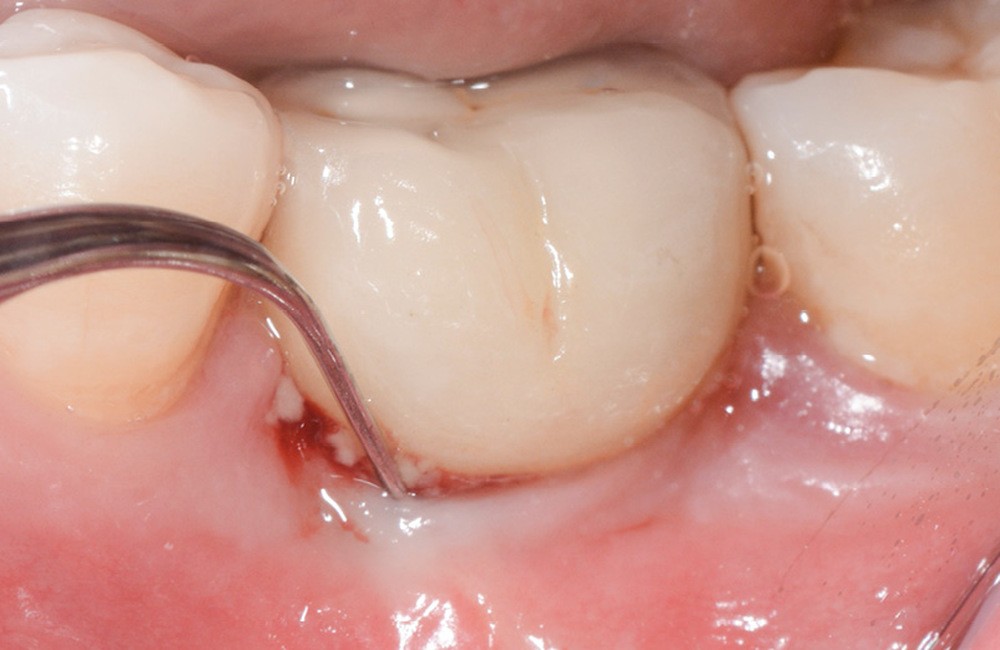

- Péri-implantite diagnostiquée en 2021

Chez ce patient, le traitement de la péri-implantite a comporté une chirurgie associant décontamination électrolytique de la surface implantaire, régénération osseuse guidée et enfouissement de l’implant. Le résultat à 2 ans est très moyen au vu du pourcentage de régénération osseuse obtenu. Comment peut-on prévoir un tel résultat alors que l’on a suivi les recommandations à la lettre, que l’on a utilisé les dernières technologies de décontamination, que l’on y a mis tous les moyens, que le patient est en bonne santé générale et qu’il vient en plus régulièrement aux séances de thérapeutique de soutien ? Le succès du traitement des péri-implantites n’est pas simple à obtenir, surtout quand un élément clé est compromis… la maintenance personnelle ! En effet le succès n’est possible que si le contrôle de plaque quotidien est optimal et, ici, ça n’était pas le cas. Le patient se brossait certes les dents, mais ne passait pas quotidiennement les brossettes, ce qui…